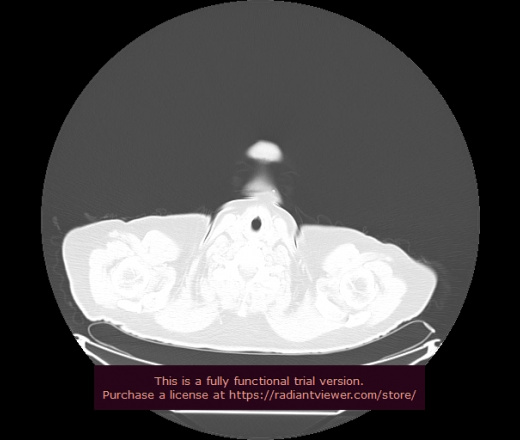

Уважаемые коллеги, если имеется интерес, сможете ли Вы спрогнозировать дальнейшее +-одинаковое течение процесса у 4 данных разных пациентов? Зацепиться где-то можно очень просто, где-то нельзя.